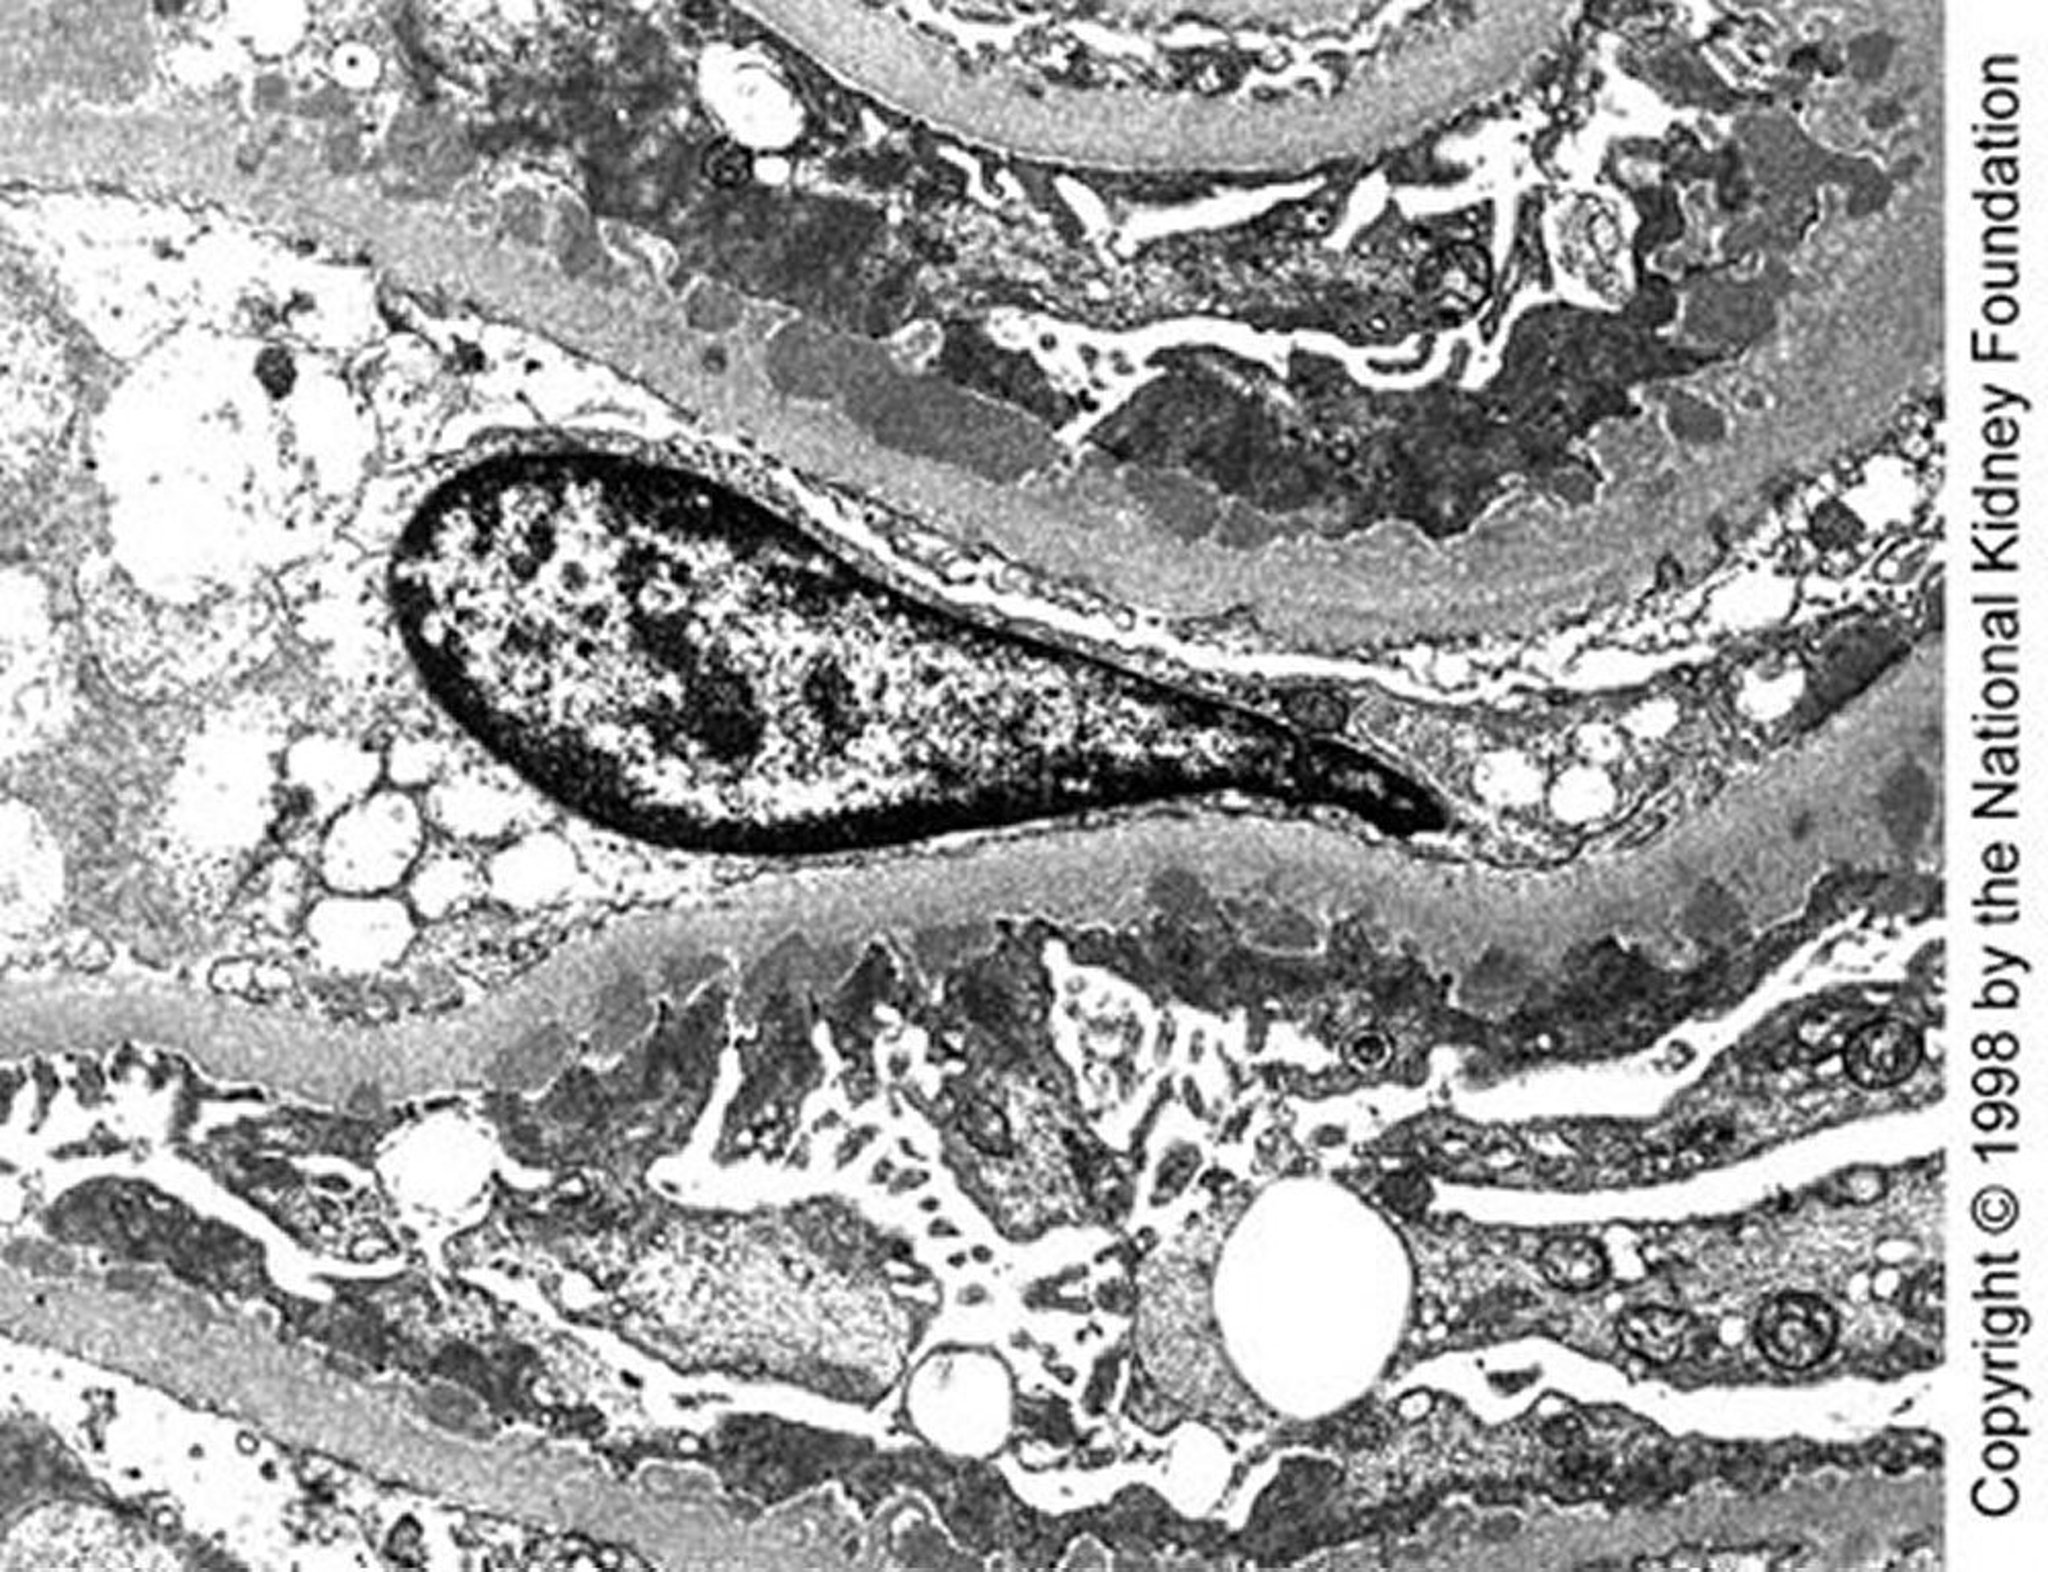

Nefropatía membranosa (depósitos densos)

En la enfermedad en estadio I avanzado se observan depósitos densos subepiteliales de tamaño mediano en la microscopia electrónica de transmisión (×10.200).

Image provided by Agnes Fogo, MD, and the American Journal of Kidney Diseases' Atlas of Renal Pathology (véase www.ajkd.org).